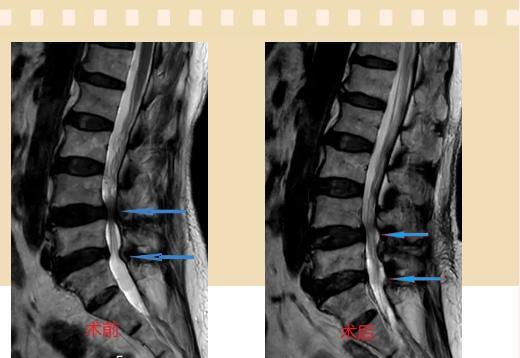

入院后李鵬副主任醫(yī)師為其進(jìn)行了詳細(xì)的查體,完善了術(shù)前的檢查,明確診斷為:腰椎管狹窄癥(L4/5、L5/S1),病人合并2型糖尿病,請(qǐng)內(nèi)分泌科會(huì)診,穩(wěn)定血糖后,麻醉科會(huì)診病人,排除手術(shù)禁忌,李鵬為病人制定了手術(shù)方案:?jiǎn)蝹?cè)入路雙側(cè)減壓(ULBD)。

手術(shù)采用三個(gè)微創(chuàng)小切口,兩個(gè)節(jié)段減壓手術(shù)時(shí)間2.5小時(shí),出血50ml。術(shù)后2天腰圍保護(hù)下床活動(dòng),術(shù)后5天順利出院。

傳統(tǒng)腰椎管狹窄癥的手術(shù)治療,往往需要切開減壓,同時(shí)需要內(nèi)固定融合術(shù),創(chuàng)傷很大,同時(shí)可能需要輸血,臥床時(shí)間較長(zhǎng),病人合并糖尿病,感染風(fēng)險(xiǎn)也高,而本次采用的UBE-ULBD手術(shù)切口更?。悠饋砑s3cm,如果是單節(jié)段狹窄只需要不到2cm切口)、創(chuàng)傷更小,術(shù)后恢復(fù)較快,可以更早地恢復(fù)正?;顒?dòng)。

此外,手術(shù)保留了病變節(jié)段的穩(wěn)定性,是一種微創(chuàng)的椎管減壓手術(shù),能通過切除部分椎板、關(guān)節(jié)突關(guān)節(jié)、黃韌帶來解除神經(jīng)根和硬膜囊的壓迫,不需要額外行腰椎內(nèi)固定術(shù),不需要螺釘及融合器的植入,病人術(shù)后腰椎的活動(dòng)度不受影響。(盧   闖  劉   旭   袁錦鈺)